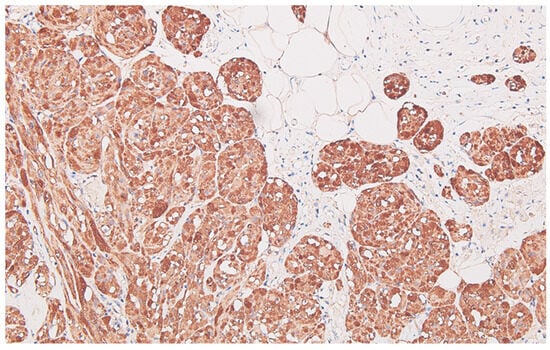

Collision Tumors of the Colon and Peritoneum: Signet-Ring Cell Carcinoma and Granular Cell Tumor

2. Case Report

Histopathological Findings